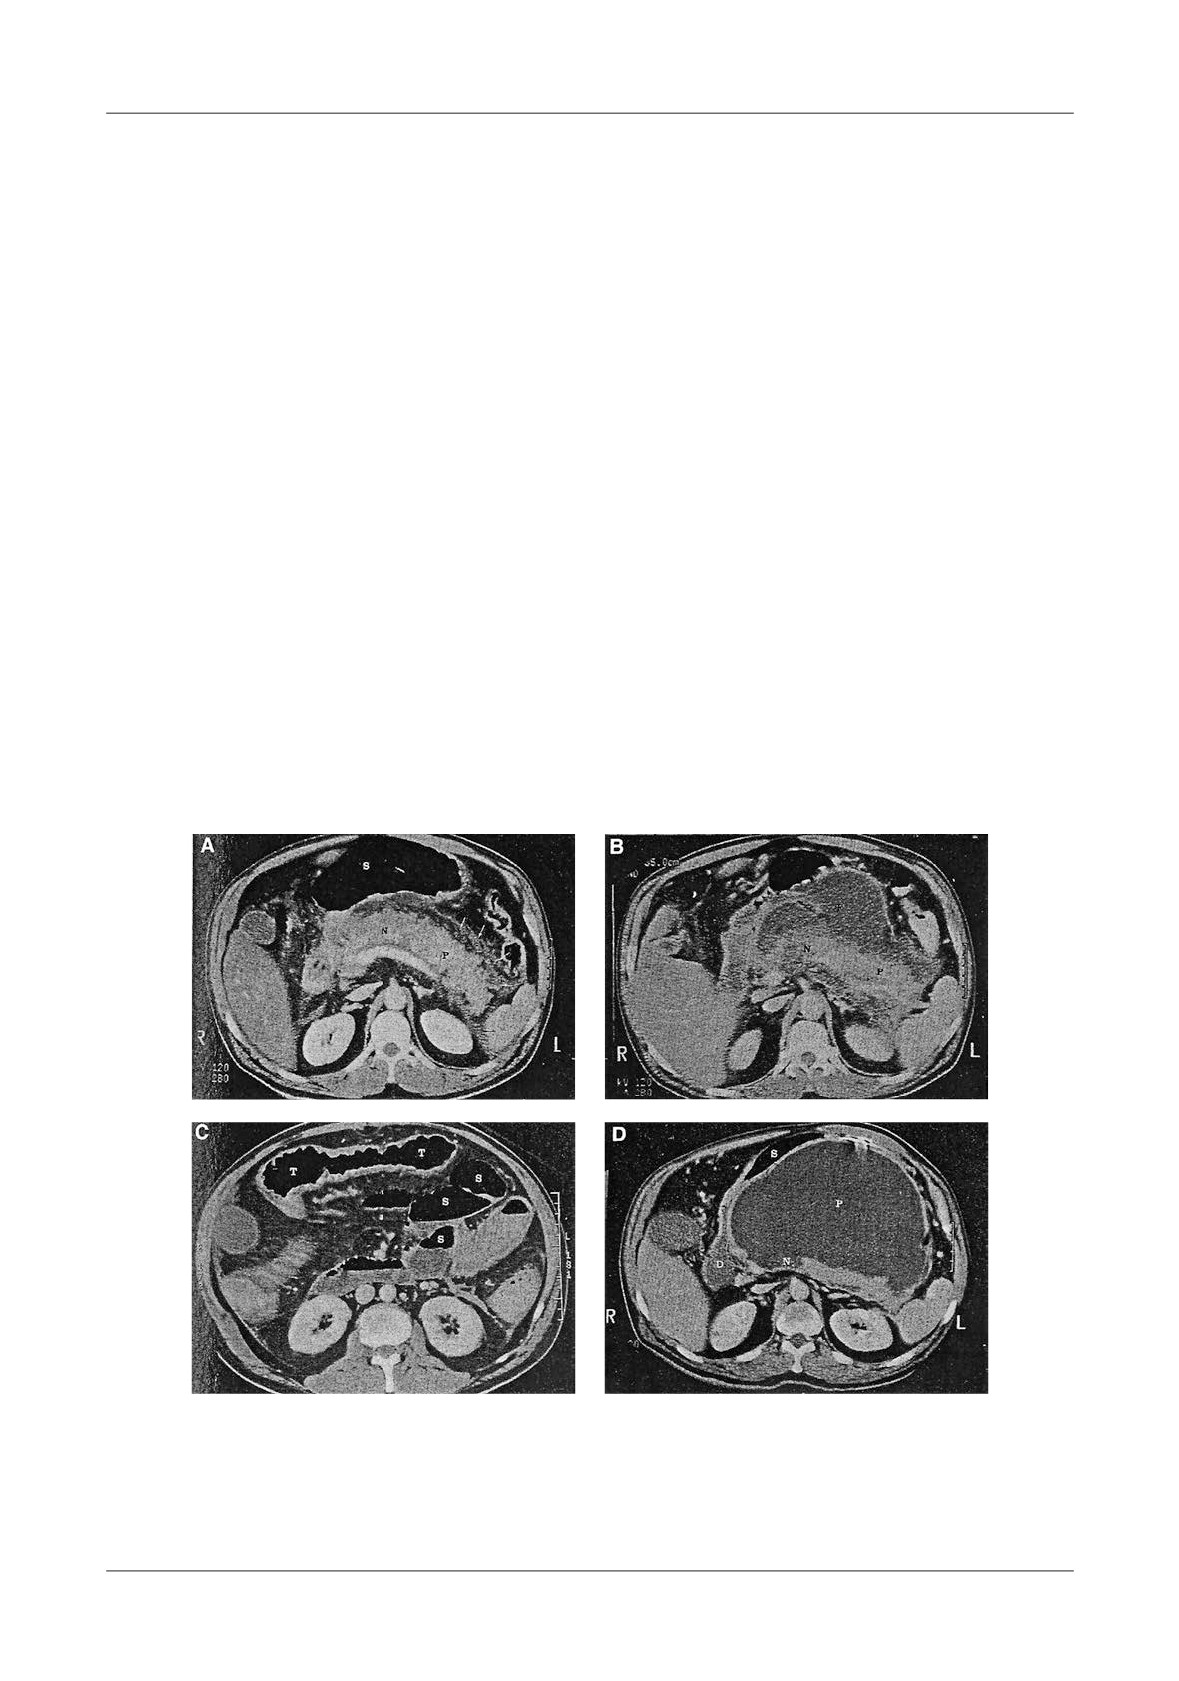

Figure 1. Pancreatic necrosis with the development of a pseudocyst, ileus and colonic in ltration in a 38

-year-old man. A-At admission the CT- shows enlarged pancreas and peripancreatic in ammation,  uid

(N=necrosis, P=pancreas, S=stomach), B-Lique ed necrosis nine days later with partially encapsulated

uid collection in the lesser sac, C-Dilated small bowel loops, with a haustral transverse colon. S=small

bowel, T=transverse colon, D-Five weeks later, fully encapsulated pseudocyst in the lower sac, with

lique ed necrosis in the neck of the pancreas (D=duodenum, N=necrosis, P=pseudocyst, S=stomach)

Figure 6. A - Normally enhancing pancreas with peripancreatic  uid collections (D=duodenum,

S=stomach, F= uid, P=pancreas), B - Transverse colon is air  lled and distended, C - Native

abdominal  lm showing distension of transverse colon

Figure 7. Intrasplenic and subcapsular

Figure 8. Splenomegaly and gastric varices with

hemorrhage (H=hemorrhage, S=spleen,

two episodes of pancreatitis. Massive enlarged

P=pancreas)

spleen, with peripheral infarct

Figure 9. Infarcted right colon in A.P. A-CT image shows pseudocyst with pancreatic necrosis

6 weeks following AP, B-One month later CT showed late pneumocystosis